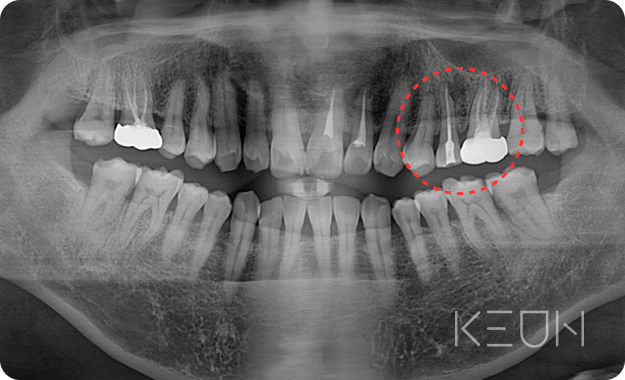

- Before

- After

신경 재치료

신경치료 근관의 개수, 길이, 굵기 등을 측정한 후 치수를 제거하고 근관을 세척해 미세한 근관까지 소독한 후 근관 충전을 하는 방식으로 치료합니다. 그러나 치료 후에도 지속해서 통증이 남아있다면 신경재치료가 필요합니다.